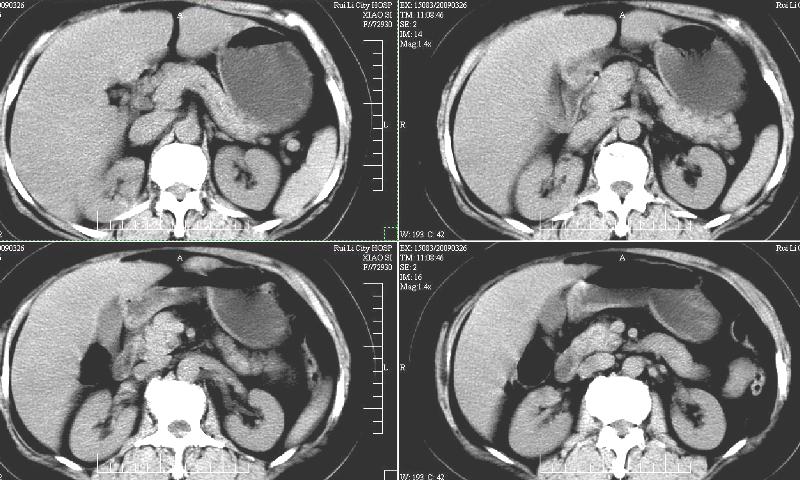

标题: CT19130:F,60岁。2008-10-17CT发现肝脏占位,现在复查! [打印本页]

标题: CT19130:F,60岁。2008-10-17CT发现肝脏占位,现在复查!

前次已经增强,所以这次没有增。ct:肝右叶平滑肌血管脂肪瘤治疗后复查,肿瘤大小同前或略有缩小。2、轻度脂肪肝。3、肝左叶小囊肿

支持楼主意见,肝右叶平滑肌血管脂肪瘤。